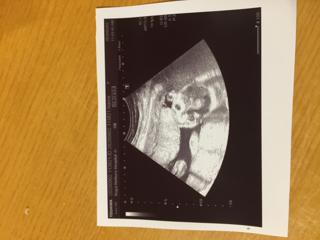

一卵性の双子です。初めてツーショットが撮れました。380gと400gです。身長は2人とも25cm。順調です!